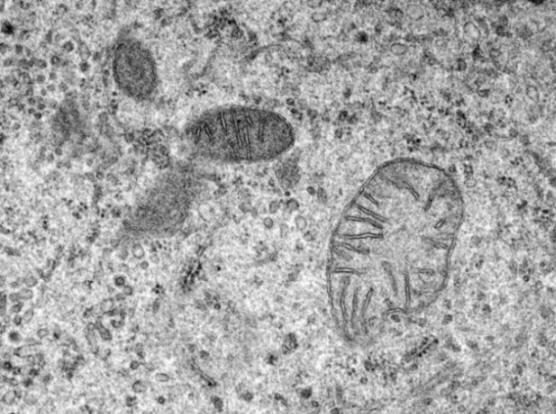

8. Как работят митохондриите?

снимка от открити източници

Митохондриите са неразделна част от нашето тяло. Единствената цел на микроскопичните органели е да трансформират всички храната, която консумираме в енергия. Много дълго време не знаехме митохондриите не са почти нищо, но науката е близо до разбирането как те работят.

Съвсем наскоро учените научиха как митохондриите носят енергия. Учените също научиха, че митохондриите наистина харесват калция, т.е. което понякога може да доведе до проблеми: ако митохондриите абсорбират твърде много калций, той може да убие клетките. Това се дължи на заболявания като диабет тип 2.

Изследователите смятат, че тези заболявания засягат процесът на предаване на сигнали, чрез които тялото комуникира митохондрии, колко калций се абсорбира и колко се отделя. Наскоро изследователски екип от Харвард успя да въведе каталог на всеки протеин в митохондриите, включително всички протеини, свързан с усвояването на калция. Засега има малко информация, но тази предстои да разрешим мистерията.